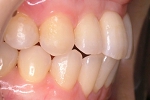

CASE4

前歯で物が噛み切れない。 顔が曲がって見える。

右のアゴが たまに痛い。

(19歳/女性)↓

||||||||

概要・担当医コメント:

開咬/下顎の左右的偏位/顎関節症/非抜歯

動的治療期間28ヶ月(28回)/費用概算:65万円

顎関節症の改善を主目的として治療を開始しました.歯科矯正用アンカースクリューを使用することにより,上下とも非抜歯で治療出来ました.大臼歯の上下的位置を調整することで,顎関節に負担のかかり過ぎない噛み合わせにしました.